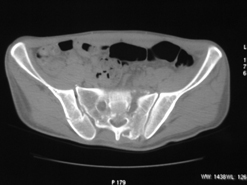

Диагноз : Сочетанная травма. ЗЧМТ. Перелом свода черепа. Ушиб головного мозга.Разрыв лонного и крестцово-подвздошного сочленений с нарушением целостности тазового кольца, с массивной забрюшинной гематомой и пропотеванием в брюшную полость. Перелом 10 ребра справа, осложненный гемопневмотораксом справа, правосторонней пневмонией на фоне ушиба правого легкого. Шок 3-4 ст. Больной поступил в отделение 07.03.2005г. в 16.00 в экстренном порядке через 30 минут после автодорожной травмы.Доставлен КСП. При поступлении состояние больного крайне тяжелое, явления травматического шока, А/Д-80/60 мм.рт. ст. ЧСС-120.В экстренном порядке поднят в операционную, интубирован, совместно с диагностическими мероприятиями лечение шока.При осмотре выявлены перелом 10 ребра справа, разрыв лонного и правого крестцово-подвздошного сочленений. Имеется линейный перелом теменной и височной костей слева с переходом на основание. Диагностическая лапароскопия 07.03.2005г. в 16.30-массивная забрюшинная гематома малого таза.Оставлена контрольная, дренажная трубка.Учитывая кровь в моче произведена цистография - данных за разрыв мочевого пузыря не найдено. Больной переведен в реанимационное отделение.За 08.03.2005г. из брюшной полости выделилось до 1500,0 мл, крови, часть крови реинфузирована. 08.03. в 06.30 наложен торокоцентез справа,удалено 100,0 мл. крови и 200,0 мл. воздуха .. Учитывая продолжающеееся кровотечение в брюшную полость из перелома костей таза, для исключения возможного разрыва внутренних органов 09.03.2005г. произведена Видеолапароскопия., на которой повреждения органов брюшной полости не выявлено.Одновременно произведен шов лонного сочленения проволокой и винтами, с одномоментным наложением стержневого аппарата на кости таза, с целью уменьшения кровотечения из разрывов тазовых сочленений, дренирование гематом. В последующем состояние больного оставалось тяжелым. 10.03.наложена нижняя трахеостома.Далее неоднократно производилась лечебно-диагностическая ФБС.С 10.03 выявлена правосторонняя плевропневмония. КТ головного мозга от 10.03-субарахноидальноекровоизлияние.Срединные структуры не смещены. КТ-контроль от 15.03-открытая моновентрикулярная гидроцефалия4 желудочка. Полисинусит. Постепенно состояние больного медленно прогрессировало к улучшению.С 24.03 переведен на самостоятельное дыхание, а 09.03 переведен в травматологическое отделение.Аппарат стержневой снят из-за перелома стержня (раскрутил больной самостоятельно).После госпитализации в наше отделение проведено дополнительное обследование Рентгекнография, КТ.Хотелось бы услышать Ваше мнение о дальнейшей тактике.-- С уважением, Leonid

Углядел билатеральное повреждение таза. Имеется вертикальная нестабильность со стороны перелома боковой массы крестца, ротационная с контрлатеральной стороны - чрезподвздошный разрыв кп сочленения. Разрыв лона, запирательные отверстия вроде целы.

DS. на сегодняшний день: Вертикальная двусторонняя нестабильная деформация таза, неправильно срастающийся перелом боковой массы крестца слева, срастающийся перелом крыла правой подвздошной кости, застарелый частичный разрыв правого кп сочленения, застарелый разрыв лонного сочленения.

План жизни - оперативное лечение. ЧКО таза (кольцевая опора), последовательная фиксация задних отделов с низведением перелома крестца, синтез лона пластинами, илиосакральное блокирование.